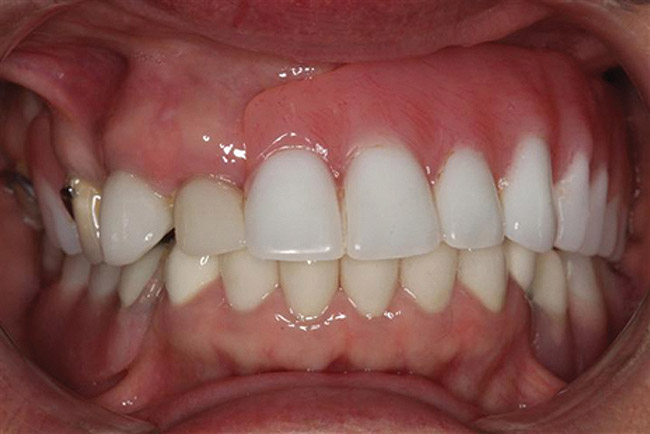

Figure 10  Postoperative images of the patient’s restorative smile.

Figure 10

Upon delivery, the prosthesis was screwed into the implants and torqued to 15 Ncm. The screw access hole was filled with a plugging material to within 1 mm of the top of the sleeve. Composite material was then used to bring the screw access hole level with the surface acrylic. The procedure was repeated for the lower denture (Figure 10 and Figure 11).